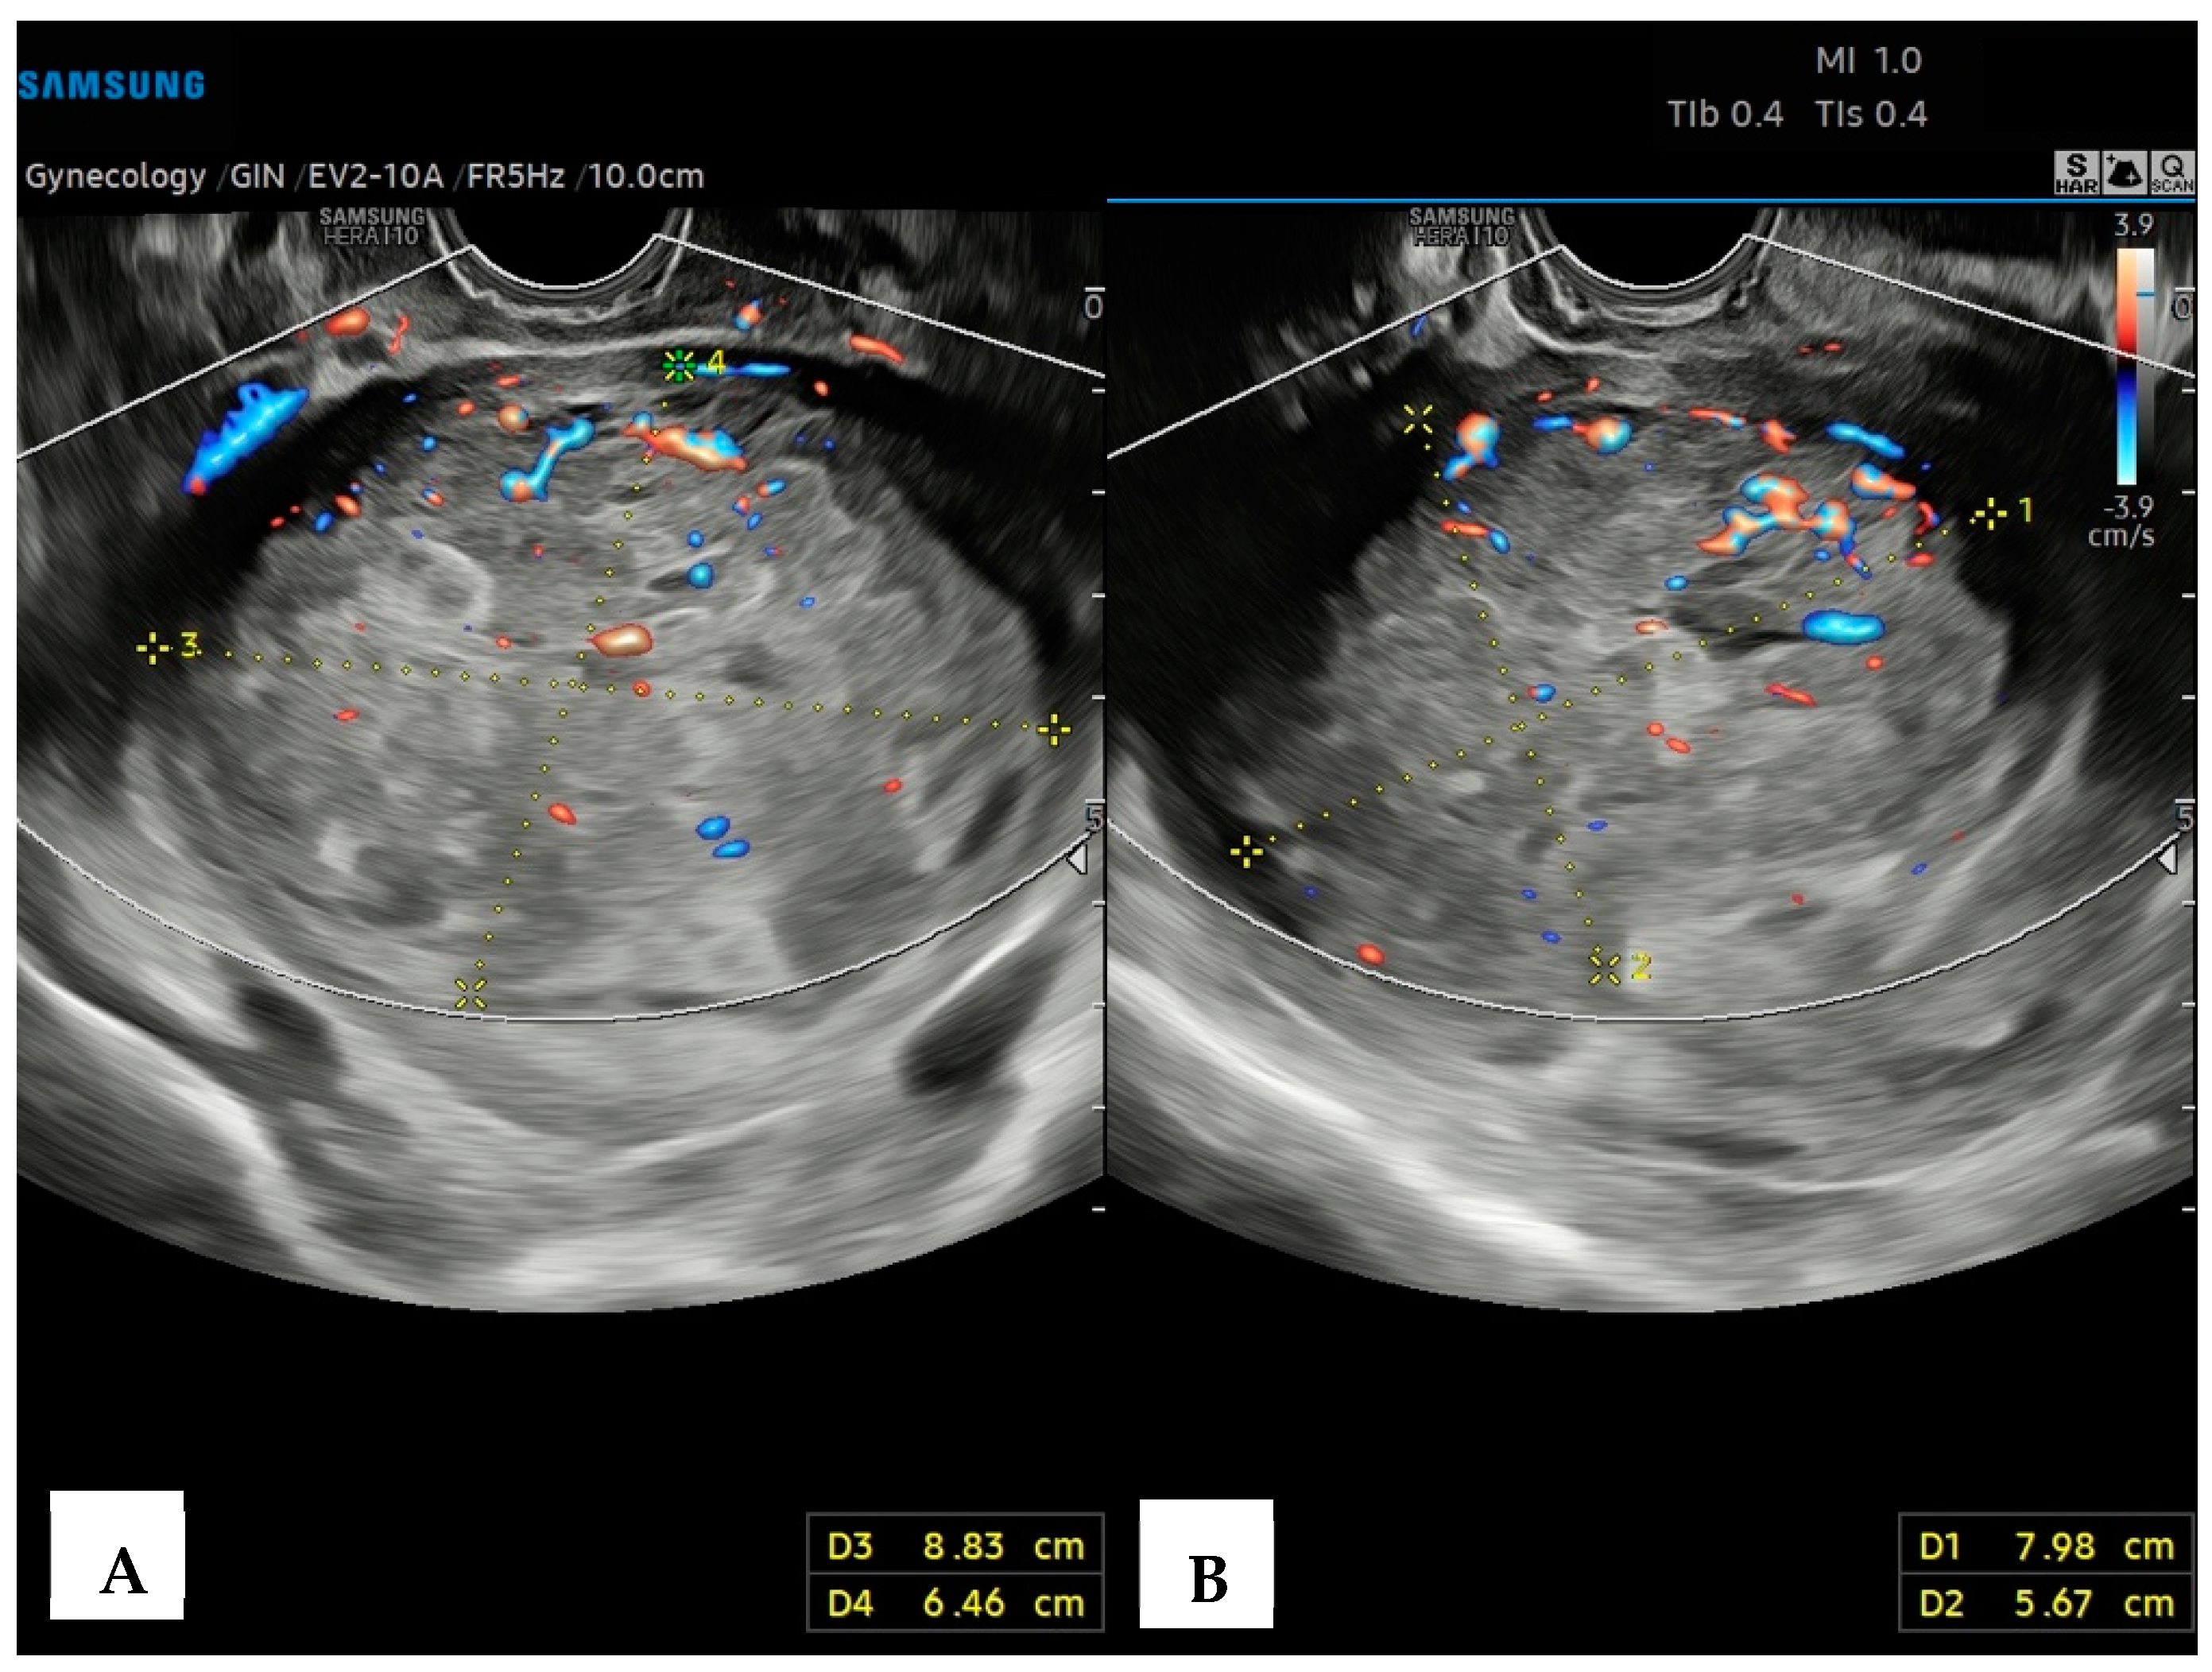

The preoperatory hypothesis was an atypical myoma or adenomyoma, in volumetric growth >50% compared to the previous control 3 months earlier. The adnexa, pouch of Douglas, pelvic peritoneum, and the pelvic tract of ureters were regular. On the left parauterine side, an elongated solid hypoechoic formation, with defined contours, abundant intralesional vascularization on the CD image (CS4), and extension toward the ovarian fossa, measuring 6.7 × 1.6 × 2.5 cm, was described (Figure 2). Pelvic Magnetic Resonance Imaging (RMI) confirmed the atypical myometrial lesion, without parauterine nor adnexal anomalies. Serum tumor markers (LDH, CEA, CA125, CA19.9, He4) were normal.

Figure 2. Transvaginal ultrasound with Color Doppler analysis; the longitudinal plane shows a solid elongated, hypoechoic, left parauterine mass. The Color Doppler analysis emphasizes the intense vascularization of the lesion.